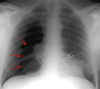

Radiographic Findings in Pulmonary Embolism (PE)

Due to its relative lack of sensitivity, the chest x-ray in patients with suspected pulmonary embolism is usually relegated to the role of ruling out other disorders which may have a similar clinical presentation. The chest x-ray is also very useful when interpreting ventilation-perfusion scans. Though the majority of patients with pulmonary embolism in retrospect do have abnormalities on the chest x-ray, findings are usually too non-specific to be of diagnostic value. Without infarction there are few chest film signs of pulmonary emboli. These include discoid atelectasis, elevation of the hemidiaphragm, enlargement of the main pulmonary artery into what has been described as the shape of a “sausage” or a “knuckle” (Palla’s sign), and pulmonary oligemia beyond the point of occlusion (Westermark’s sign). Occasionally, pulmonary embolisms will cause infarction causing a unique constellation of radiographic signs. Multifocal consolidation of the affected lung may occur in 12 to 24 hours following the embolic event. A consolidation which begins at the pleural surface and is rounded centrally is called a Hamptom’s Hump. These types of consolidation differ from pneumonia in that they lack air bronchograms. Up to 50% of patients with pulmonary embolism will also have ipsilateral or bilateral pulmonary effusions, although these are certainly nonspecific findings. Nevertheless, it is unusual for pulmonary infarctions to be diagnosed by chest radiography although infarctions are known to occur much more frequently. Presumably infarcts are confused with or indistinguishable from atelectasis or pneumonia. Despite the low sensitivity of these signs, the chest radiograph remains an important first step in the diagnosis of pulmonary embolism, primarily to exclude other causes of hypoxemia and to aid in the interpretation of the ventilation/perfusion scan.

May see: Westermark’s sign (oligemia in area of involvement), increased size of a hilum (caused by thrombus impaction), atelectasis with elevation of hemidiaphragm and linear or disk shaped densities, pleural effusion, consolidation, and Hampton’s hump (rounded opacity). In the case of pulmonary infarctions, the main radiographic feature is multifocal consolidation at the pleural base in the lower lungs.